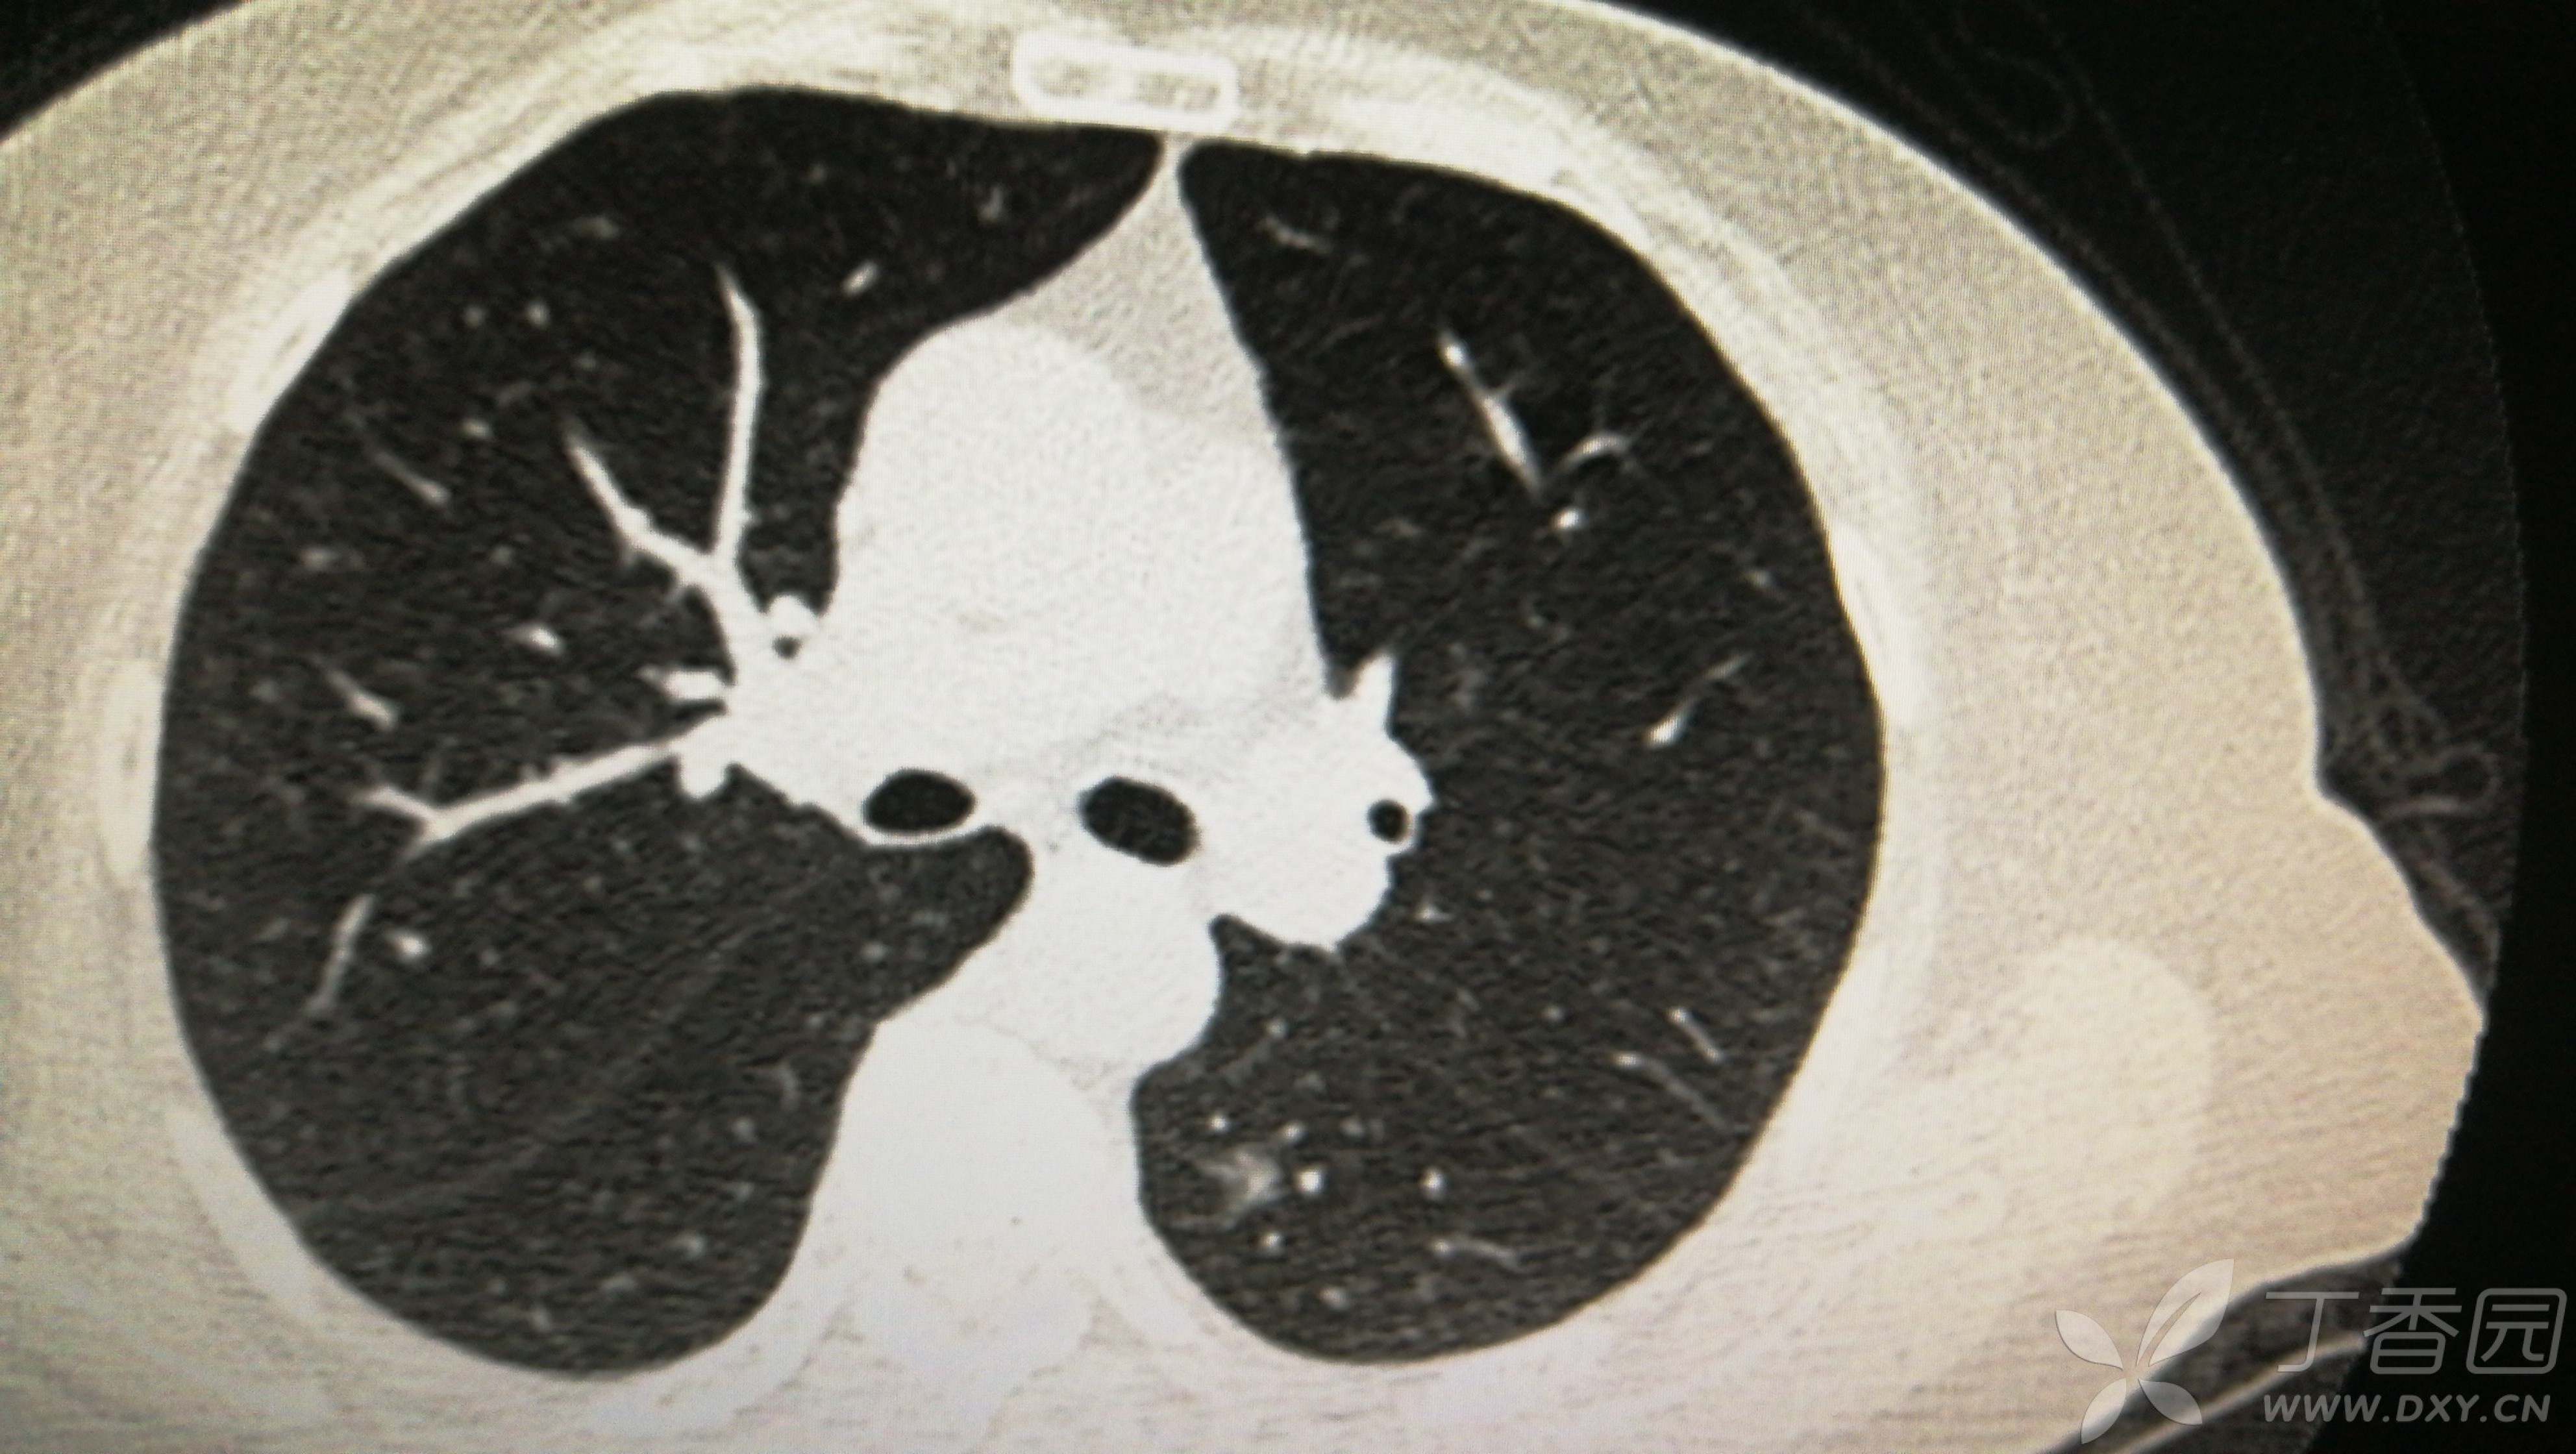

①双肺多发磨玻璃结节

②右下肺实性结节